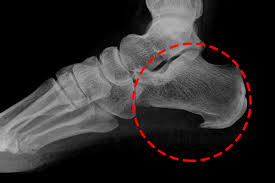

이 질환은 발밑의 족저근막에 염증이 생겨 발뒤꿈치에서 발가락까지 이어지는 섬유띠가 영향을 받는 질환으로, 중장년층 뿐만 아니라 젊은 세대에게도 흔하게 발생합니다.

족저근막염은 다양한 원인이 있습니다. 발의 구조적인 이상인 평발이나 요족 등이 원인일 수 있지만, 대부분은 발을 과도하게 사용하여 발생합니다.

족저근막염은 발바닥의 근막에 염증이 생기는 흔한 발목 문제 중 하나입니다. 이 질환은 다양한 증상을 동반하며 환자들에게 불편함을 초래합니다. 주요 족저근막염의 증상은 다음과 같습니다: